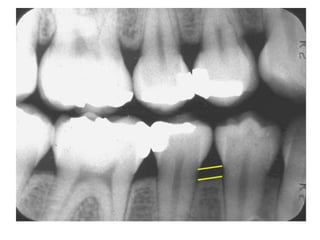

Bitewing Radiographs

• It is a lateral projection of tooth crown in both

jaws on same side.

• It is very useful in delectation of incipient

proximal caries and state of restoration.

• It can be taken by using film size no. 0 or 1 or

young children and no. 2 for older children.

• The coronal portion of both maxillary and

mandibular teeth visualized on the film.

Bitewing Radiographs • Itis a lateral projection of tooth crown in both jaws on same side. • It is very useful in delectation of incipient proximal caries and state of restoration. • It can be taken by using film size no. 0 or 1 or young children and no. 2 for older children. • The coronal portion of both maxillary and mandibular teeth visualized on the film.